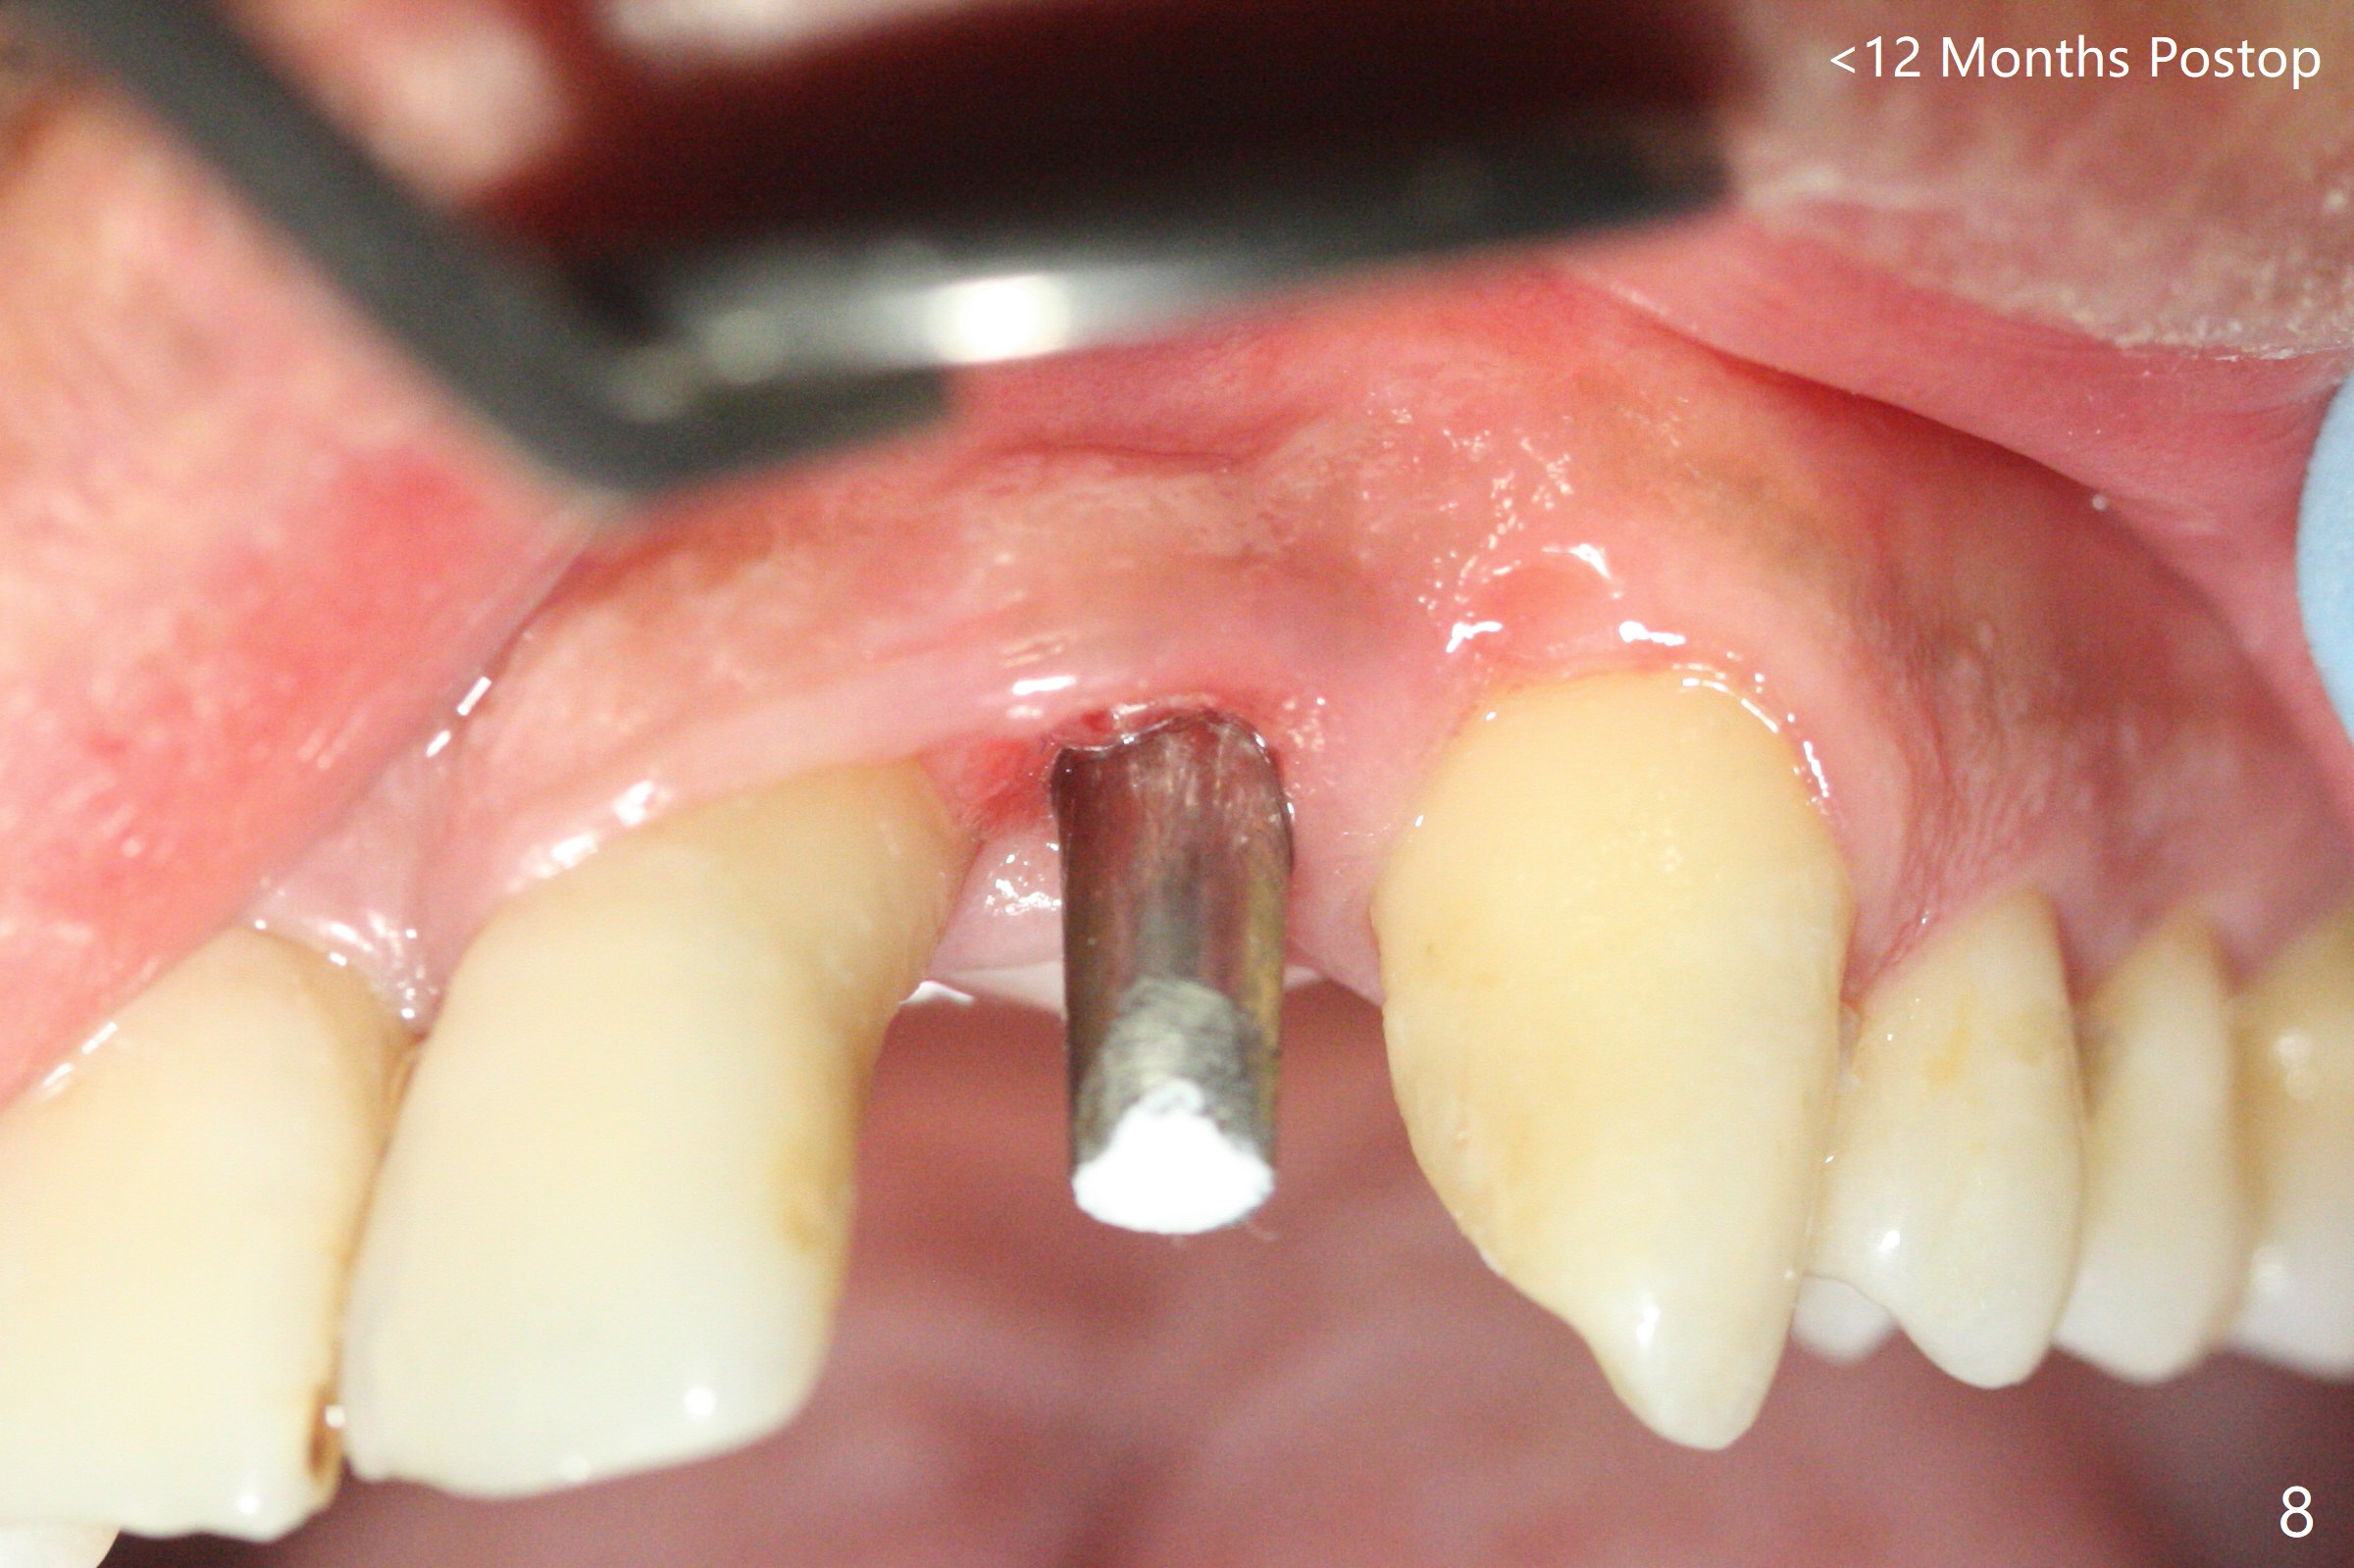

实验结果表明红管抽取上清液形成粘性骨块比白管快。左上二拔除,即刻徒手钻洞(图一),初步植入3.8x11.5毫米植体(图二),调整植体深度,然后放置直径4.5毫米长基台(图三,DIO UF; 牙龈厚度大于6毫米),最后填入大量粘性骨粉(图四,五 *),植体颊侧近中骨粉不足(图五 ^),之后再次充填骨粉。制作即刻修复物,颊侧瘘道和牙槽窝开口放置PRF膜。术后三周临时牙冠松动,取出后者,颊侧空间有两个区域:牙龈和骨粉(图六:白,黑星号)。由于脑部手术,术后接近一年病人回来取模。由于基台长,临时牙冠还没有脱落(图八)。牙龈袖正常(图九:*)。术后一年骨粉仍在植体,基台交界处(图十)。